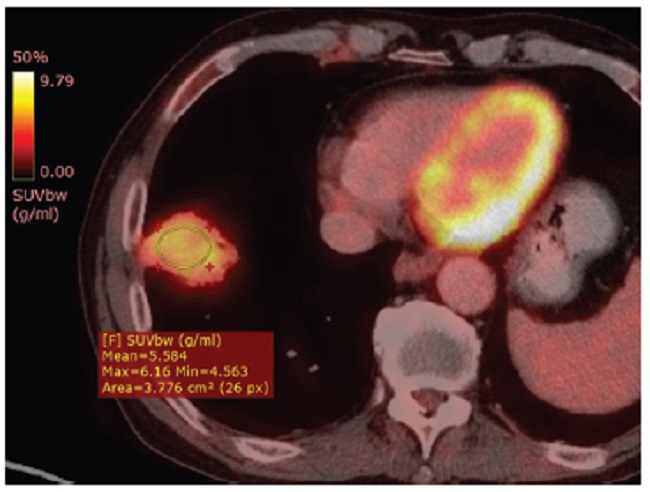

Presentamos el caso de un hombre de 67 años con diagnóstico reciente de carcinoma epidermoide queratinizante orofaríngeo, que en TC y PET-TC de estadificación presentó imagen pulmonar, consolidativa, en contacto con la cisura mayor y el domo diafragmático, con fino broncograma aéreo y reticulación perilesional (Fig. 1). Esta lesión demostró ser hipermetabólica con un SUV de 5,5 (Fig. 2). Dados los hallazgos, se realizó biopsia percutánea guiada por TC para confirmar secundarismo. Sin embargo, se identificó infiltración por población linfocitaria B de pequeño tamaño con perfil inmunohistoquímico positivo para CD20, bcl2 y Kappa, resultando negativo con CD3, CD5, Ciclina D1, CD10 y Lambda (Fig. 3). La citometría de flujo arrojó linfocitos B: 45,32%, población patológica: 96,06%, CD19+, CD20+, CD10-, CD5-, kappa+, CD23-, y CD43+ débil. Se arribó entonces al diagnóstico de infiltración por linfoma B de la zona marginal extraganglionar (MALT). Realizó tratamiento de inducción con esquema docetaxel, 5-fluouracilo y cisplatino. Luego consolidación con radioterapia y carboplatino concurrente. En la nueva PET-TC, seis meses más tarde, se pudo apreciar disminución de la captación de 18-fluorodesoxiglucosa (18F-FDG) y del tamaño de la lesión pulmonar (Fig. 4).